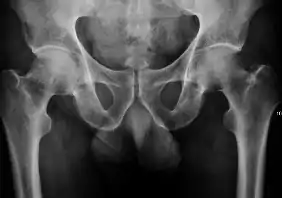

- Osteoarthritis

In adults, one of the main indications for radiographs is the detection of osteoarthritic changes (Figure 1(e)). Nevertheless, radiographs usually detect advanced osteoarthritis that can be graded according to the Tönnis classifications. The grading system ranges from 0 to 3, where 0 shows no sign of osteoarthritis. Intermediate grade 1 shows mild sclerosis of the head and acetabulum, slight joint space narrowing, and marginal osteophyte lipping. Grade 2 presents with small cysts in the femoral head or acetabulum, moderate joint space narrowing, and moderate loss of sphericity of the femoral head. Grade 3 is the severest form of osteoarthritis, which manifests as severe narrowing of the joint space, large subchondral cyst with productive bone changes that may lead to deformity of the bone components of the joint, while secondary osteoarthritis due to calcium pyrophosphate deposition can be diagnosed when calcification of hyaline cartilage and fibrocartilage is detected.[1]

There are other pathological conditions that can affect the hip joint and radiographs help to make the appropriate diagnosis. Acute bacterial septic arthritis can be diagnosed by radiographs when a fast regional osteoporosis and destructive monoarticular process develops (Figure 1(f)). In case of tuberculous or brucella arthritis it is manifested as a slow progressive process, and diagnosis may be delayed.[1]